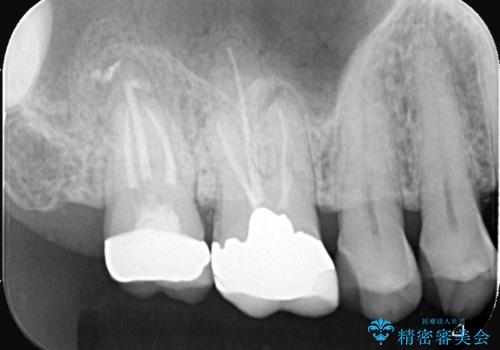

根尖性歯周炎|歯根嚢胞|インプラント治療

- 治療計画

- 右上7番に瘻孔を認め、根管治療を実施しましたが、瘻孔が再発し治癒が得られなかったため、抜歯のうえインプラントによる補綴治療を行いました。

抜歯と歯根嚢胞の除去を行った後、インプラントで治療しました。治療後は「自分の歯のように咬める」と大変ご満足いただけました。